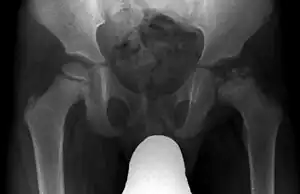

| Radiograph of a person with Legg–Calvé–Perthes disease | |

X-rays of the hip may suggest and/or verify the diagnosis. X-rays usually demonstrate a flattened, and later fragmented, femoral head. A bone scan or MRI may be useful in making the diagnosis in those cases where X-rays are inconclusive. Usually, plain radiographic changes are delayed six weeks or more from clinical onset, so bone scintigraphy and MRI are done for early diagnosis. MRI results are more accurate, i.e. 97–99% against 88–93% in plain radiography. If MRI or bone scans are necessary, a positive diagnosis relies upon patchy areas of vascularity to the capital femoral epiphysis (the developing femoral head).[11]